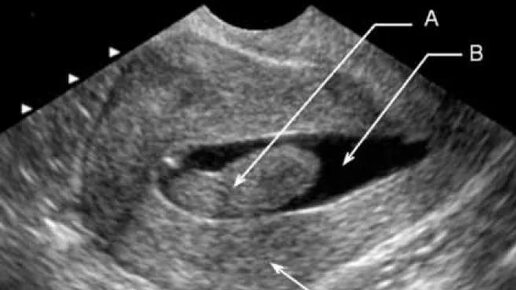

Полип – это доброкачественное нарастание из фиброзной ткани на эндометрии матки либо шейке. Новообразования могут быть единичными или множественным, размерами от 1-2 мм, до пары сантиментов. Обычно полипы имеют форму гриба. Как лечить? Что такое полипы? Развитие болезни Что провоцирует Полипоз в матке – это заболевание изучение не до конца. Точно установлено, что болезнь развивается у женщин, которые имеют: • Нарушения женского гормонального баланса, а именно высокий уровень эстрогена и низкий уровень прогестерона; • Нарушения работы щитовидной железы; • Инсулинозависимый диабет; • Лишний вес...